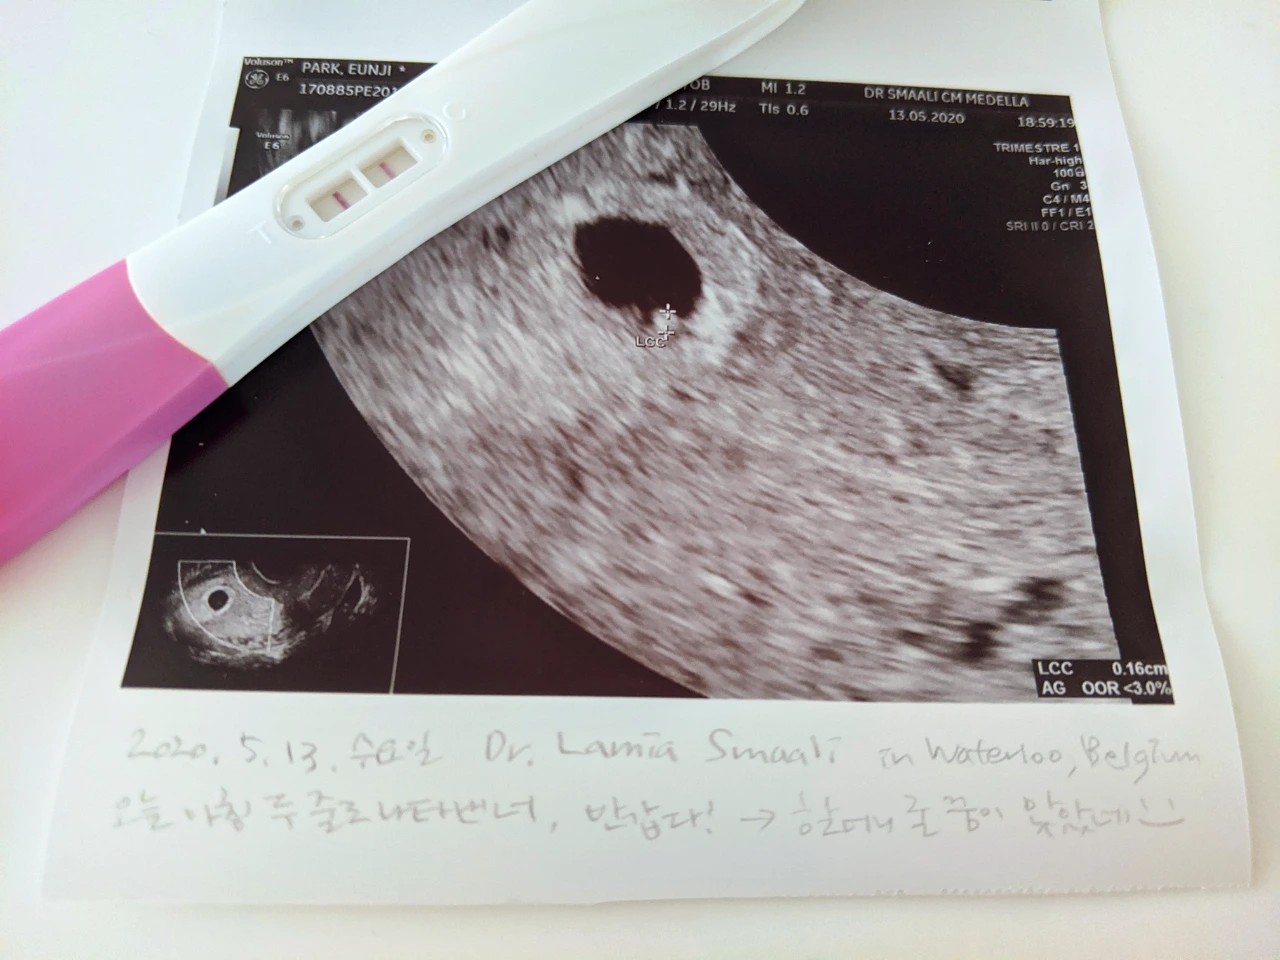

엄마는 원래 생리주기가 일정하지 않아서 몸이 아파오는 걸 느끼고 나서야, '아, 때가 왔나 보다'하고 생각해. 그런데 이번에는 온갖 증상이 다 나타나고 나서 몇 주가 지나도 아무런 소식이 없더라고. 그래서 2주 전 즈음, 혹시나 하는 마음에 집에 있던 임신 테스트기로 검사를 해 봤는데, 결과가 나타나는 첫 번째 칸이 별 반응 없이 지나가고 두 번째 칸에만 빨간 줄이 생겼어. 결과는 비임신이었지. 어차피 임신 일리가 없다는 생각으로 해 본 검사라, 그러려니 하며 흘려보냈어.

그러다 시간이 흐르고 감기몸살처럼 몸은 더 아파오는데 아직도 생리 소식이 없어, '혹시나 모르니까 한 번 더 검사해보자' 하는 마음으로 오늘 아침 다시 테스트기를 꺼내어 화장실로 갔어. 아무런 기대 없이 테스트 결과를 기다리는데, 두둥! 1초도 지나지 않아 비어있던 두 칸이 모두 빨간색 선으로 선명해졌지 뭐야. 기쁘면서도 너무 갑작스러운 소식이라 잠시 머릿속이 멈추는 느낌이었어. 네 오빠를 만났을 때도 비슷했던 것 같은데, 그때와 다른 점이라면 '너무 기뻐하지 말고 얼른 의사 선생님을 만나 확인부터 받자'는 생각부터 들었다는 것이었지. 그래도 아빠한테는 말해야 하니까, 오빠를 어린이집에 데려다주러 간 아빠가 돌아오는 시간에 맞춰 창문 앞에 서 있었어.

역시 두 번째라 엄마 아빠 모두 이 상황에 무엇이 가장 필요한지 금세 알 수 있었어. 엄마는 구글맵을 뒤져 오늘 바로 방문이 가능한 산부인과를 찾았어. 그리고 곱슬머리의 아랍계 이름을 가진 착한 산부인과 선생님의 입에서 '임신이네요'라는 말을 들을 수 있었지. 아빠랑 오빠도 같이 갔었으면 좋았을 텐데, 아쉽게도 지금은 코로나라는 바이러스가 전 세계를 뒤덮고 있는 중이라, 엄마 혼자 마스크를 쓰고 선생님을 뵈러 가야 했어. 콩알만 한 너의 초음파 사진과 우렁찬 심장박동 소리까지 들었는데, 그 감격적인 순간을 아빠와 나눌 수 없어 너무 아쉬웠지 뭐야.

두 줄로 찾아온 콩알만 한 너